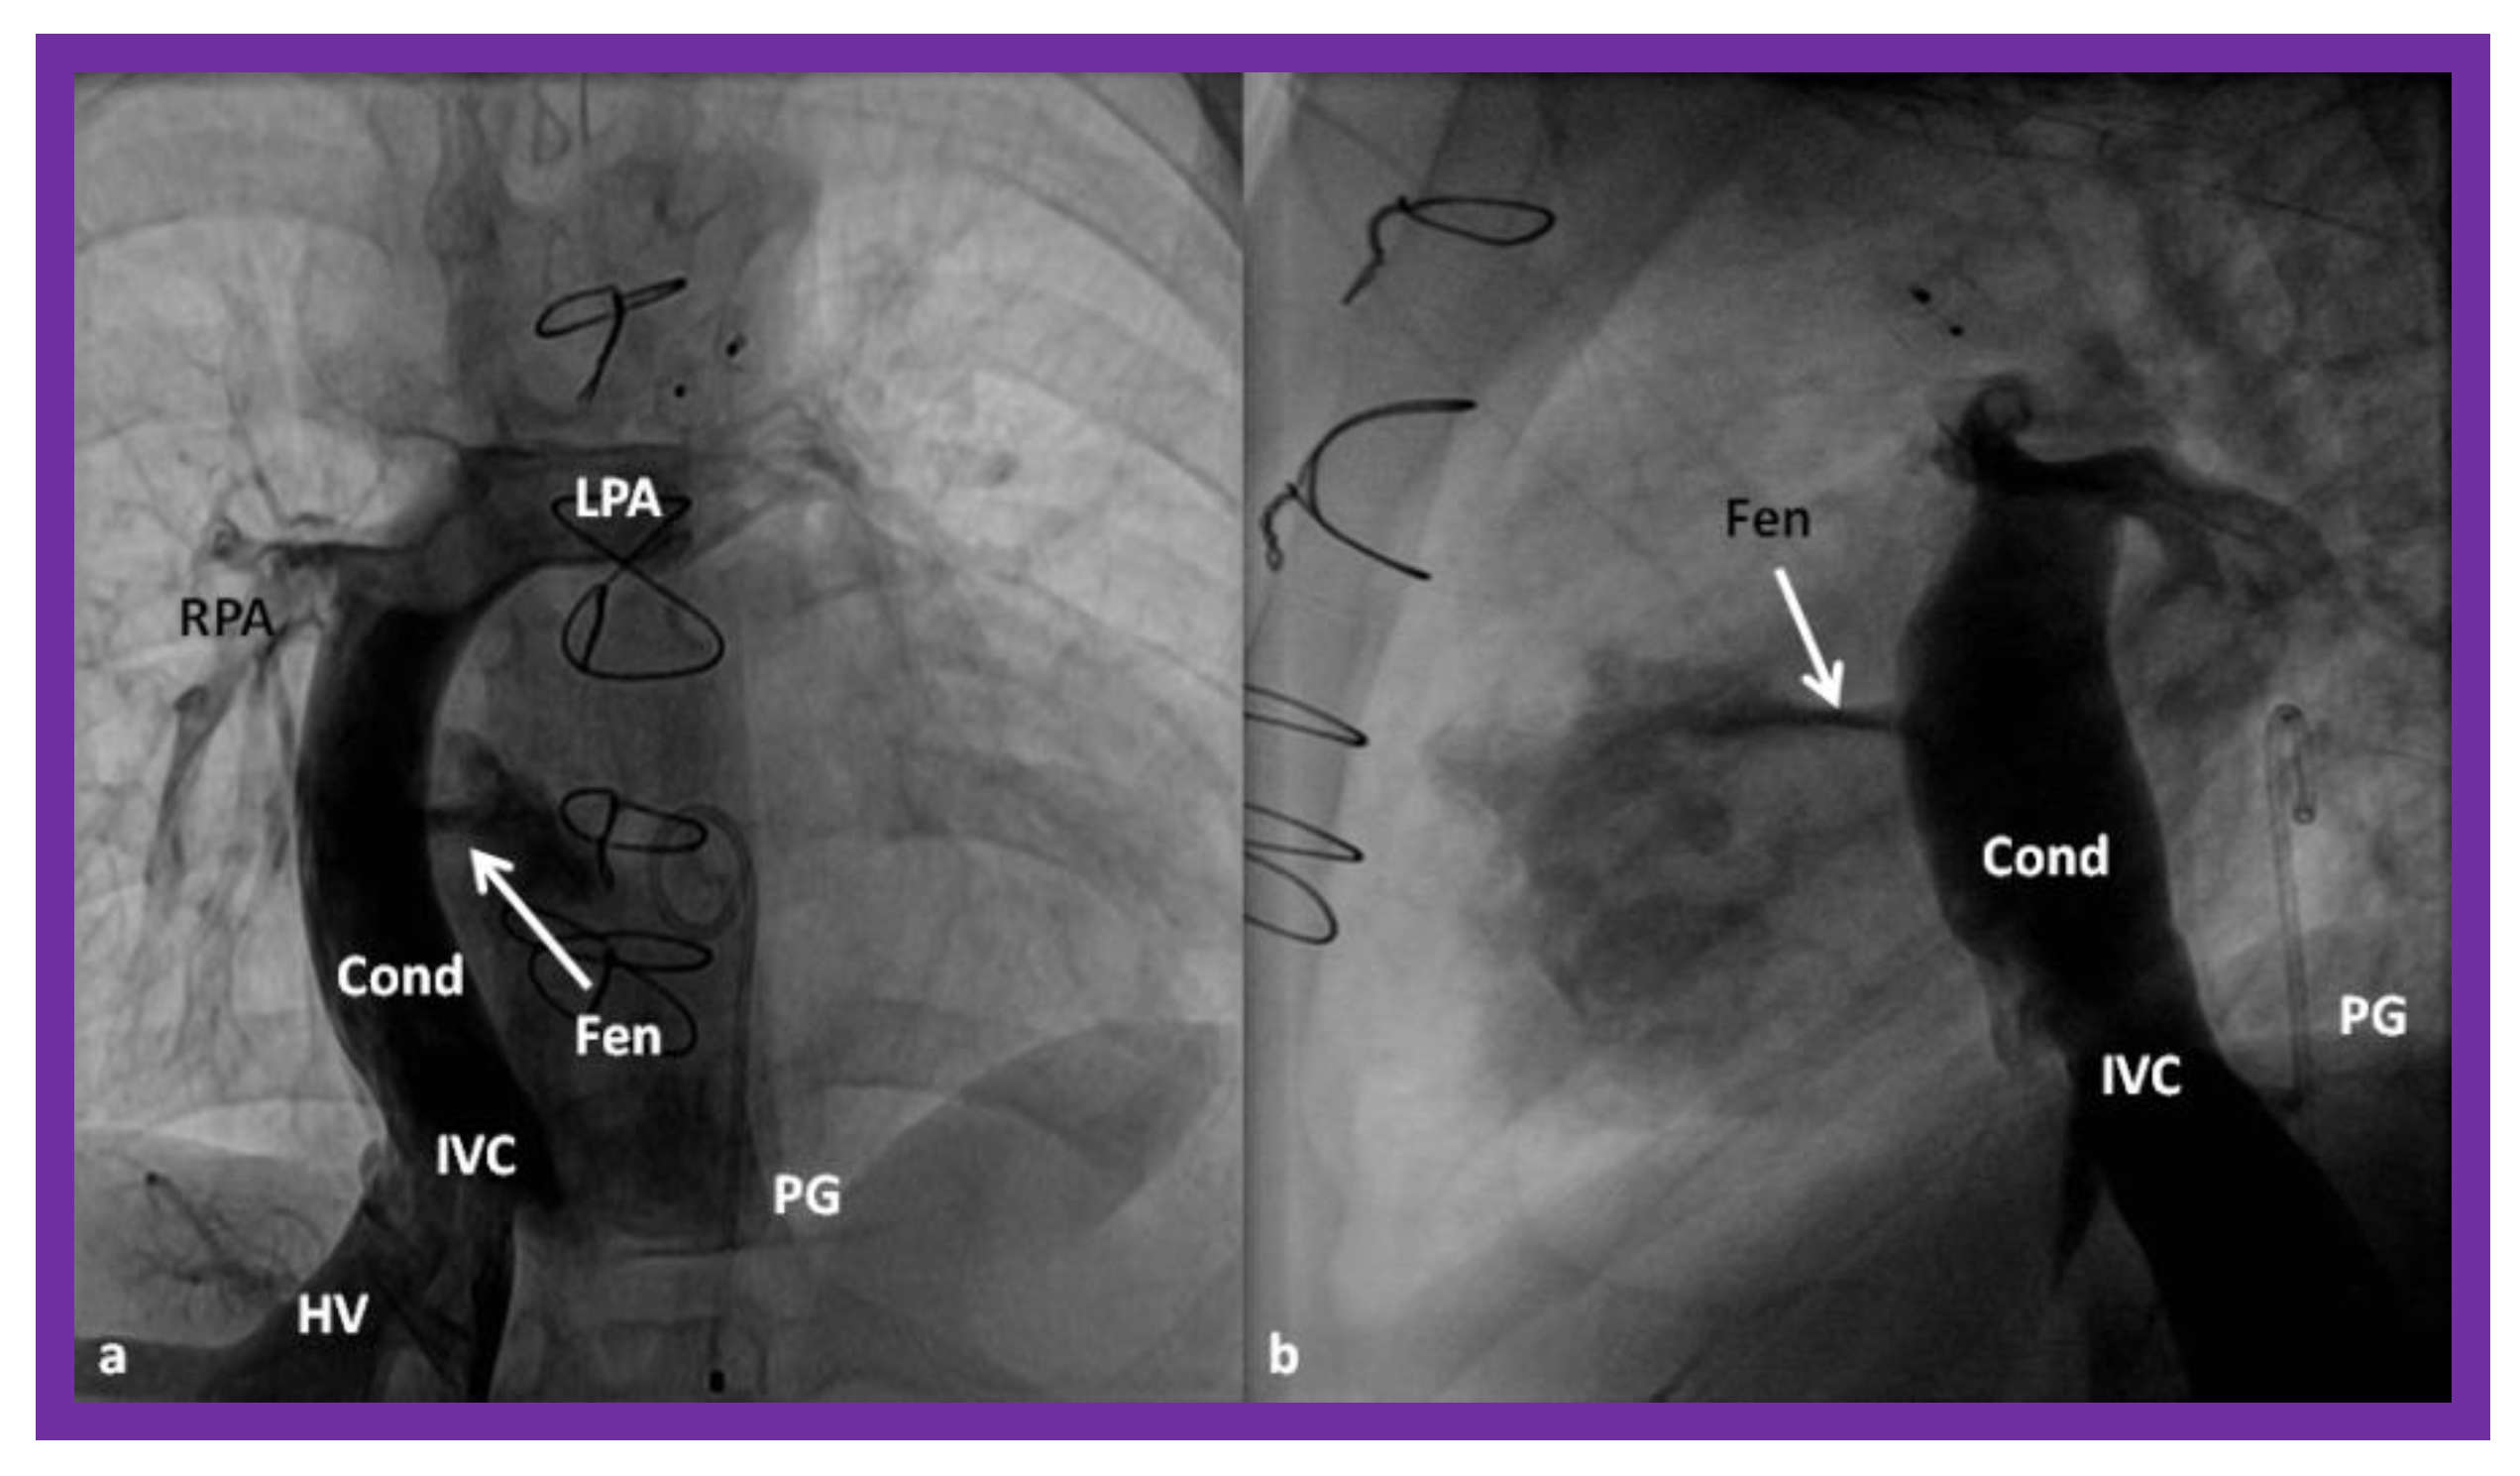

- Bridges, N.D.; Lock, J.E.; Castaneda, A.R. Baffle fenestration with subsequent transcatheter closure. Modification of the Fontan operation for patients at increased risk. Circulation 1990, 82, 1681–1689. [Google Scholar] [CrossRef] [PubMed]

- Laks, H.; Pearl, J.M.; Haas, G.S.; Drinkwater, D.C.; Milgalter, E.; Jarmakani, J.M.; Isabel-Jones, J.; George, B.L.; Williams, R.G. Partial Fontan: Advantages of an adjustable interatrial communication. Ann. Thorac. Surg. 1991, 52, 1084–1094, discussion 1094–1095. [Google Scholar] [CrossRef]

- Rao, P.S.; Chandar, J.S.; Sideris, E.B. Role of inverted buttoned device in transcatheter occlusion of atrial septal defects or patent foramen ovale with right-to-left shunting associated with previously operated complex congenital cardiac anomalies. Am. J. Cardiol. 1997, 80, 914–921. [Google Scholar] [CrossRef]

- Goff, D.A.; Blume, E.D.; Gauvreau, K.; Mayer, J.E.; Lock, J.E.; Jenkins, K.J. Clinical Advances in Complex Valvular Disease 24 outcome of fenestrated Fontan patients after closure: The first 10 years. Circulation 2000, 102, 2094–2099. [Google Scholar] [CrossRef] [PubMed]

- Boudjemline, Y.; Bonnet, D.; Sidi, D.; Agnoletti, G. Closure of extracardiac Fontan fenestration by using the Amplatzer duct occluder. Arch. des Mal. du Coeur et des Vaiss. 2005, 98, 449–454. [Google Scholar]